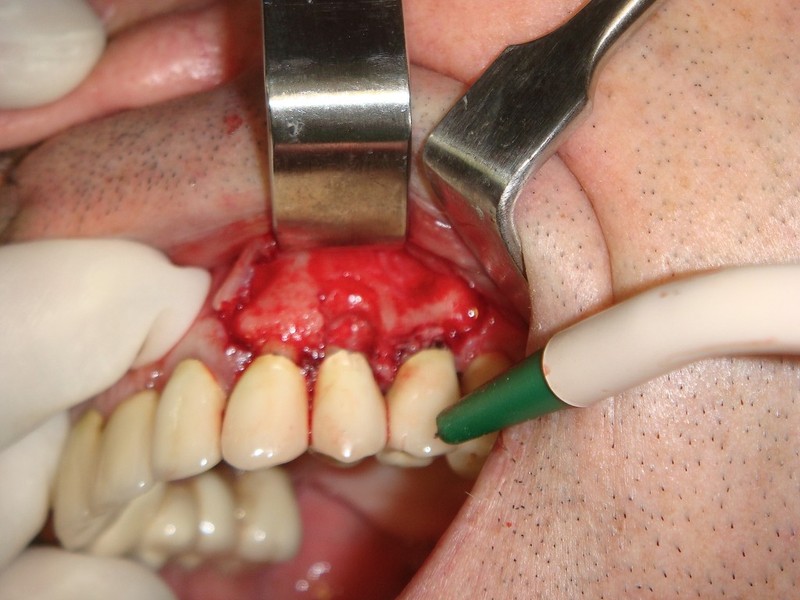

Rigenerazione Gravi difetti parodontali

Rigenerazione difetto parodontale di un canino inferiore con materiale eterologo